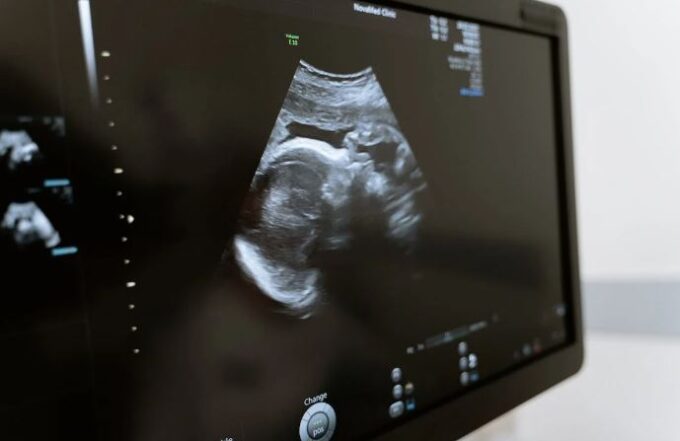

Antes de iniciar cualquier tratamiento, es crucial realizar un diagnóstico detallado. Esto puede incluir exámenes físicos, análisis de laboratorio, pruebas de imagen y, en algunos casos, procedimientos quirúrgicos menores. Este enfoque garantiza que el tratamiento sea el más adecuado para la situación específica del paciente.

Con los avances en tecnología médica, la medicina reproductiva está continuamente evolucionando. Las técnicas de diagnóstico y tratamiento son más precisas y menos invasivas que nunca, mejorando no solo las tasas de éxito sino también la experiencia del paciente.